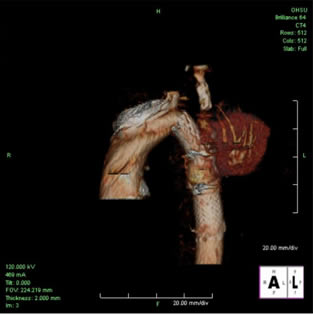

Selective angiography of the left subclavian artery was performed to confirm an intact posterior cerebral circulation. The proximal left subclavian artery was occluded with two 10mm Amplatzer vascular plugs which were introduced via the left external iliac sheath. An angiogram of the distal aortic arch and descending thoracic aorta was then performed to obtain a roadmap of the proximal and distal landing zones (Figure 4).

The tapered endoprosthesis was passed through the left external iliac sheath, positioned appropriately under fluoroscopic guidance, and deployed. An arch angiogram showed good endoprosthesis placement. Because of the relatively short proximal landing zone length (1cm), a 10 x 40mm Palmaz stent was placed and ballooned to 16mm proximally to achieve good radial fixation. The distal end of the endoprosthesis was ballooned. Completion angiography showed occlusion of the left subclavian artery and exclusion of the pseudoaneurysm (Figure 5).